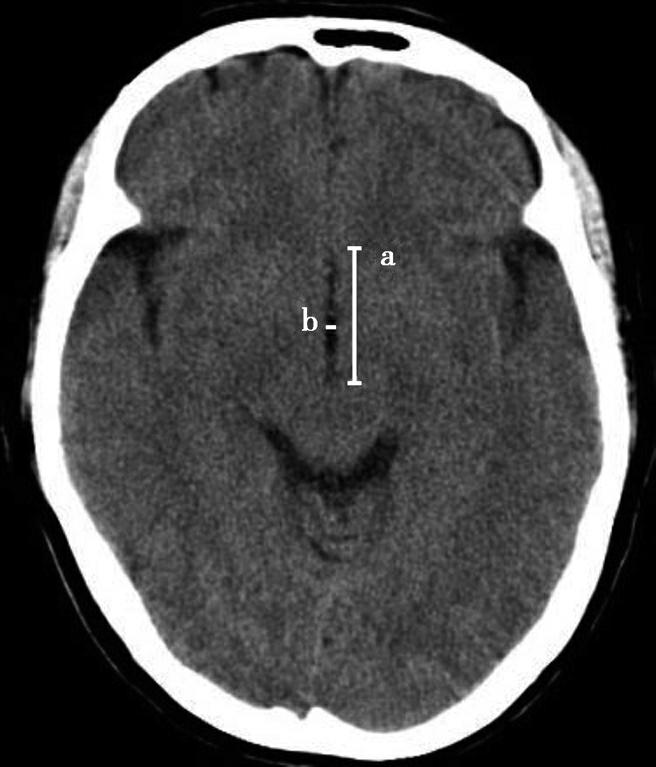

第三脑室正常成人前后径约12mm,左右宽约5mm,上下径也约为12mm。侧脑室后角两侧有时大小不等,右侧后角上下径约为38mm,左右径约为20mm;左侧后角上下径约为28mm,左右径约为15mm。测量双侧侧脑室前角间径与同平面脑横径的比值(R),正常平均值为30%。轻度扩大时为31%~39%,中度扩大为40%~46%,重度扩大时>47%。脑积水或脑萎缩等病理情况下脑室系统会扩大。不同年龄组正常脑室系统测量值存在差异,整体表现出测量值随着年龄增大而增大的趋势(图1-2-83、图1-2-84)。

图1-2-83 第三脑室测量

a线.第三脑室前后径;b线.第三脑室宽径

图1-2-84 侧脑室测量

R=双侧侧脑室前角间径(a)/同平面脑横径(b)